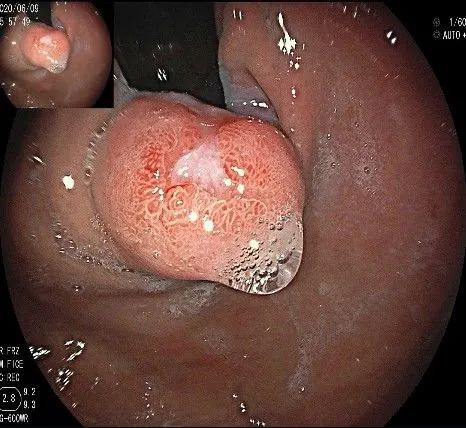

沿切开的边缘,从口侧开始向下进行粘膜下剥离,剥离的间隙是瘤体之上粘膜之下,期间反复进行粘膜下注射。

随着剥离的进行,瘤体与周围组织的关系越来越清晰。

此时瘤体基底部已暴露出来,起源于固有肌层。